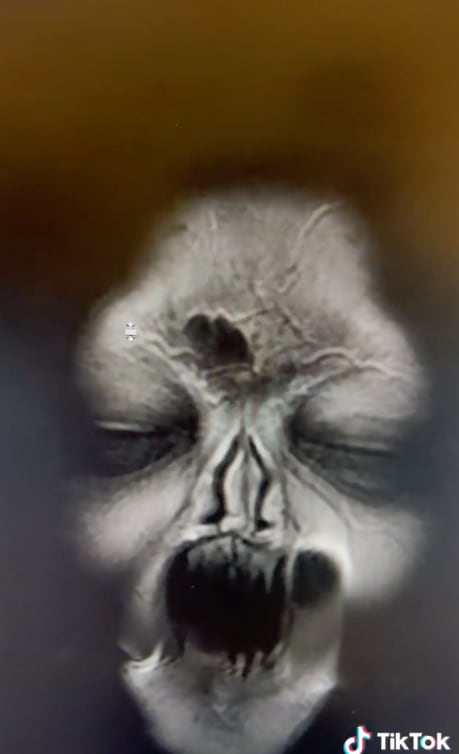

En TikTok la resonancia magnética de una señora se está haciendo viral debido a que reveló sus caras demoníacas ocultas.

Sin embargo, la resonancia magnética no solo logró su cometido, sino que dejó asustados a los usuarios de plataforma.

Y es que en las imágenes aparecieron varias caras demoníacas de la señora en lugar de una aguja dentro de su encía.

Actualmente el video cuenta con casi 3 millones de reproducciones y miles de comentarios sobre la distorsión de imágenes.